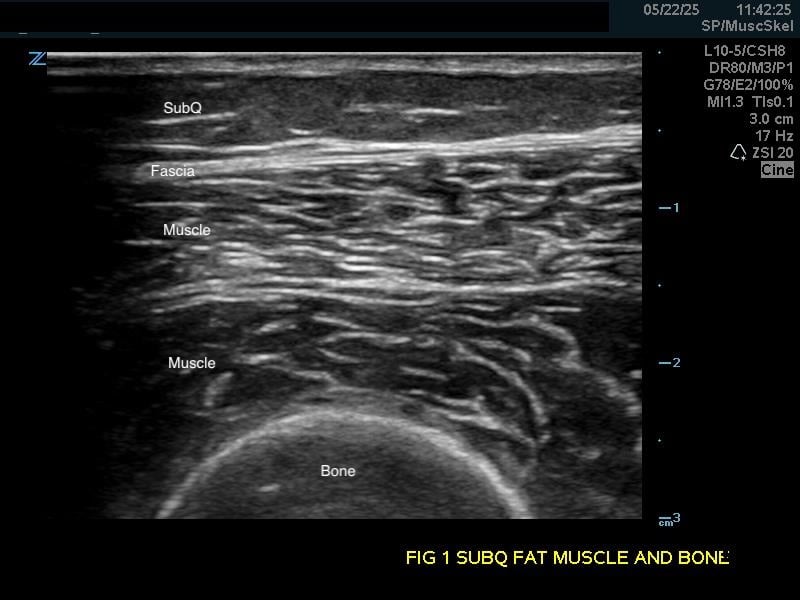

Figure 1a.

(A) Longitudinal view. Bone appears as a distinct bright echogenic line with no visible structures beneath, Subcutaneous fat appears relatively hypoechoic with thin septations of connective tissue.

Soft Tissue

Subcutaneous fat: Relatively hypoechoic with thin septations of connective tissue. The thickness of this layer varies and may require increasing the depth setting of your machine.

Muscle: Longitudinally, appears as slabs of striated hypoechoic tissue contained within the thin hyperechoic lines of fascia. Viewed transversely, muscle striations or septa appear dotted and punctate or form short lines. Fascial lines separate muscle compartments.